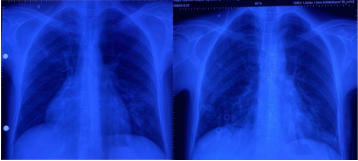

A 29-year-old male presented in outpatient department with complaints of intermittent cough with dull aching chest pain. Patient was evaluated at some Pulmonary clinic where CT (Computerized Tomography) guided lung biopsy was taken, which revealed moderate pleomorphism, mitosis present, focal hemorrhage. To differentiate better immunohistochemistry was done, which was positive for Pan CK, LCA and Ki67. It was negative for CK7, CK20, Chromogranin. CECT (Contrast Enhanced Computerized Tomography Chest) suggestive of Anterior mediastinal mass (Figure 1) 6.7x6.0x9.0 cm with SUV max 2.6 and abutting the SVC & RA. PET-CT (Positron Emission Tomography) suggestive of no distant metastasis (Figure 2). Tumor markers CA 19-9, AFP, B-HCG 1.4, CA 125 was within normal limit. Diagnosis of Type A Thymoma was established. He was planned for elective surgery. A Midline Sternotomy was performed and tumor was resected en-mass. It measured approximately 12x8 cm with areas of hemorrhage. It did not invade pleura, pericardium, heart and great vessels. Postoperative recovery was uneventful (Figure 3). He was asymptomatic at 3 months of follow up.

Figure 3: Pre and post operative Chest Xray of the patient